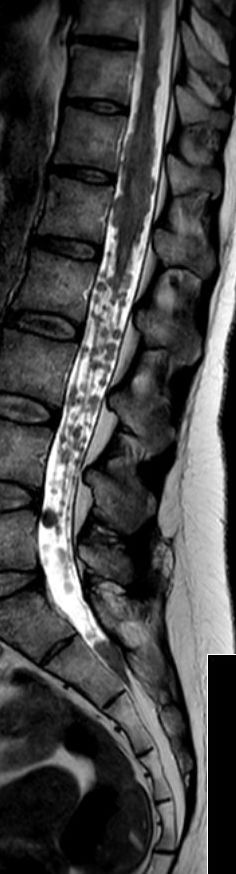

Rückenmarks-Metastasen

48-jährige Patientin mit einem kleinzelligen, neuroendokrinen Bronchialkarzinom. Taubheit der Füße, Kraftminderung und Hypästhesie beider Beine.

RM-Metastasen